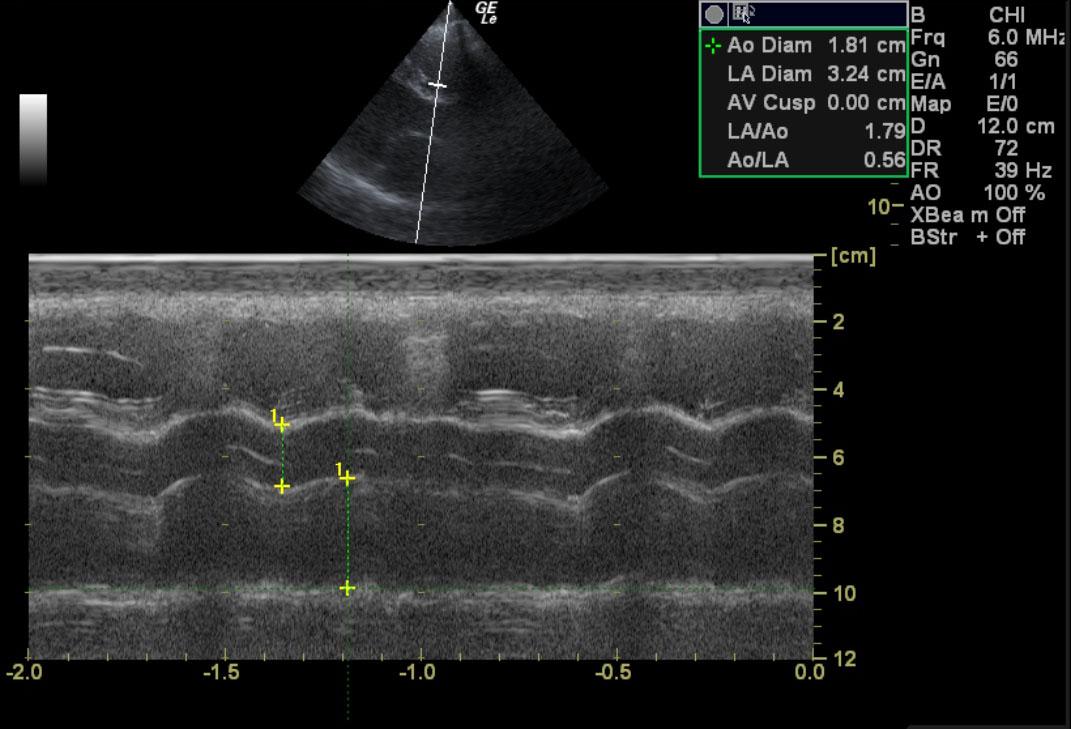

A 6-year-old NM Boxer dog was presented for lethargy, cough, tachypnea, exercise intollerance. Physical exam revelaed a 2/6 left sided heart murmur and mild tachypnea and arrhythmia. The only abnormality on laboratory work was elevated amylase and creatinine.